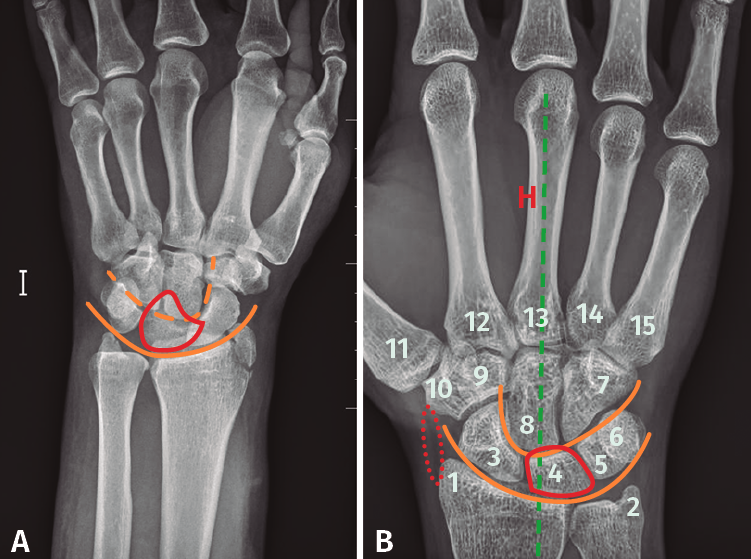

Confirmaremos el diagnóstico con una radiografía anteroposterior y lateral pura de muñeca, observándose una disrupción del arco mayor y menor del carpo, con la luxación del hueso grande de la superficie articular del semilunar y pérdida de altura del carpo. Es importante una correcta realización de las proyecciones para una buena interpretación de las mismas.

Figura 4. A: radiografía anteroposterior de luxación transestiloperilunar; B: radiografía anteroposterior sin alteraciones, recuerdo anatómico. 1: estiloides radial; 2: estiloides cubital; 3: escafoides; 4: semilunar; 5: piramidal; 6: pisiforme; 7: ganchoso; 8: grande; 9: trapecio; 10: trapezoide; 11: primer metacarpiano; 12-15: segundo a quinto metacarpianos; —: almohadilla grasa; —: eje longitudinal 3.er radio, muñeca y antebrazo; —: arcos de Gilula.

- Qué ver en una radiografía anteroposterior de muñeca (Figuras 4A y 4B). Para valorar que estamos ante una correcta proyección, debemos obtener:

– Una vista anteroposterior de la región media de los metacarpianos, del carpo, de la articulación radiocubital distal.

– La forma de la diáfisis de los metacarpianos debe ser cóncava.

– Debe existir una separación del radio y cúbito distales (puede existir una superposición mínima).

– Por último y más importante, el eje longitudinal del 3.er radio, la muñeca y el antebrazo deben quedar alineados.

En la radiografía podemos observar los siguientes ítems:

– Observar la alineación correcta de las articulaciones.

– Buscar interrupciones en las corticales de los huesos que nos puedan hacer sospechar una fractura.

– Afectación intraarticular.

– Pero, en especial, debemos fijarnos en los arcos de Gilula, deben formar 3 líneas continuas, sin disrupciones. En las luxaciones se pierde la continuidad de las líneas que forman los diferentes arcos.

- 1.er arco: superficie proximal del escafoides, semilunar y piramidal.

- 2.º arco: superficie distal del escafoides, semilunar y piramidal.

- 3.er arco: superficie proximal de grande y ganchoso.